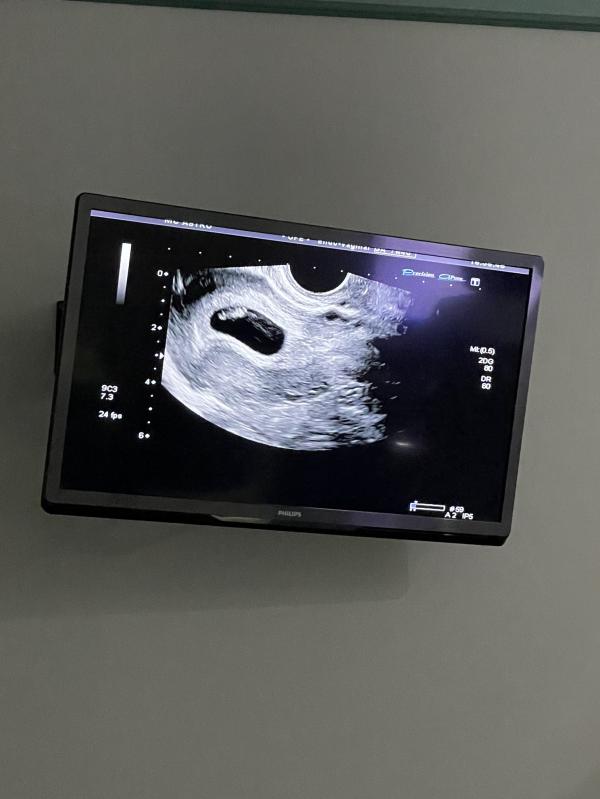

Позже была на УЗИ и узнала, что все хорошо ☺️

Услышала сердечко, чуть не расплакалась🥺🥺 это очень мило и трогательно 😭

Срок 7 недель и 1 день🥰